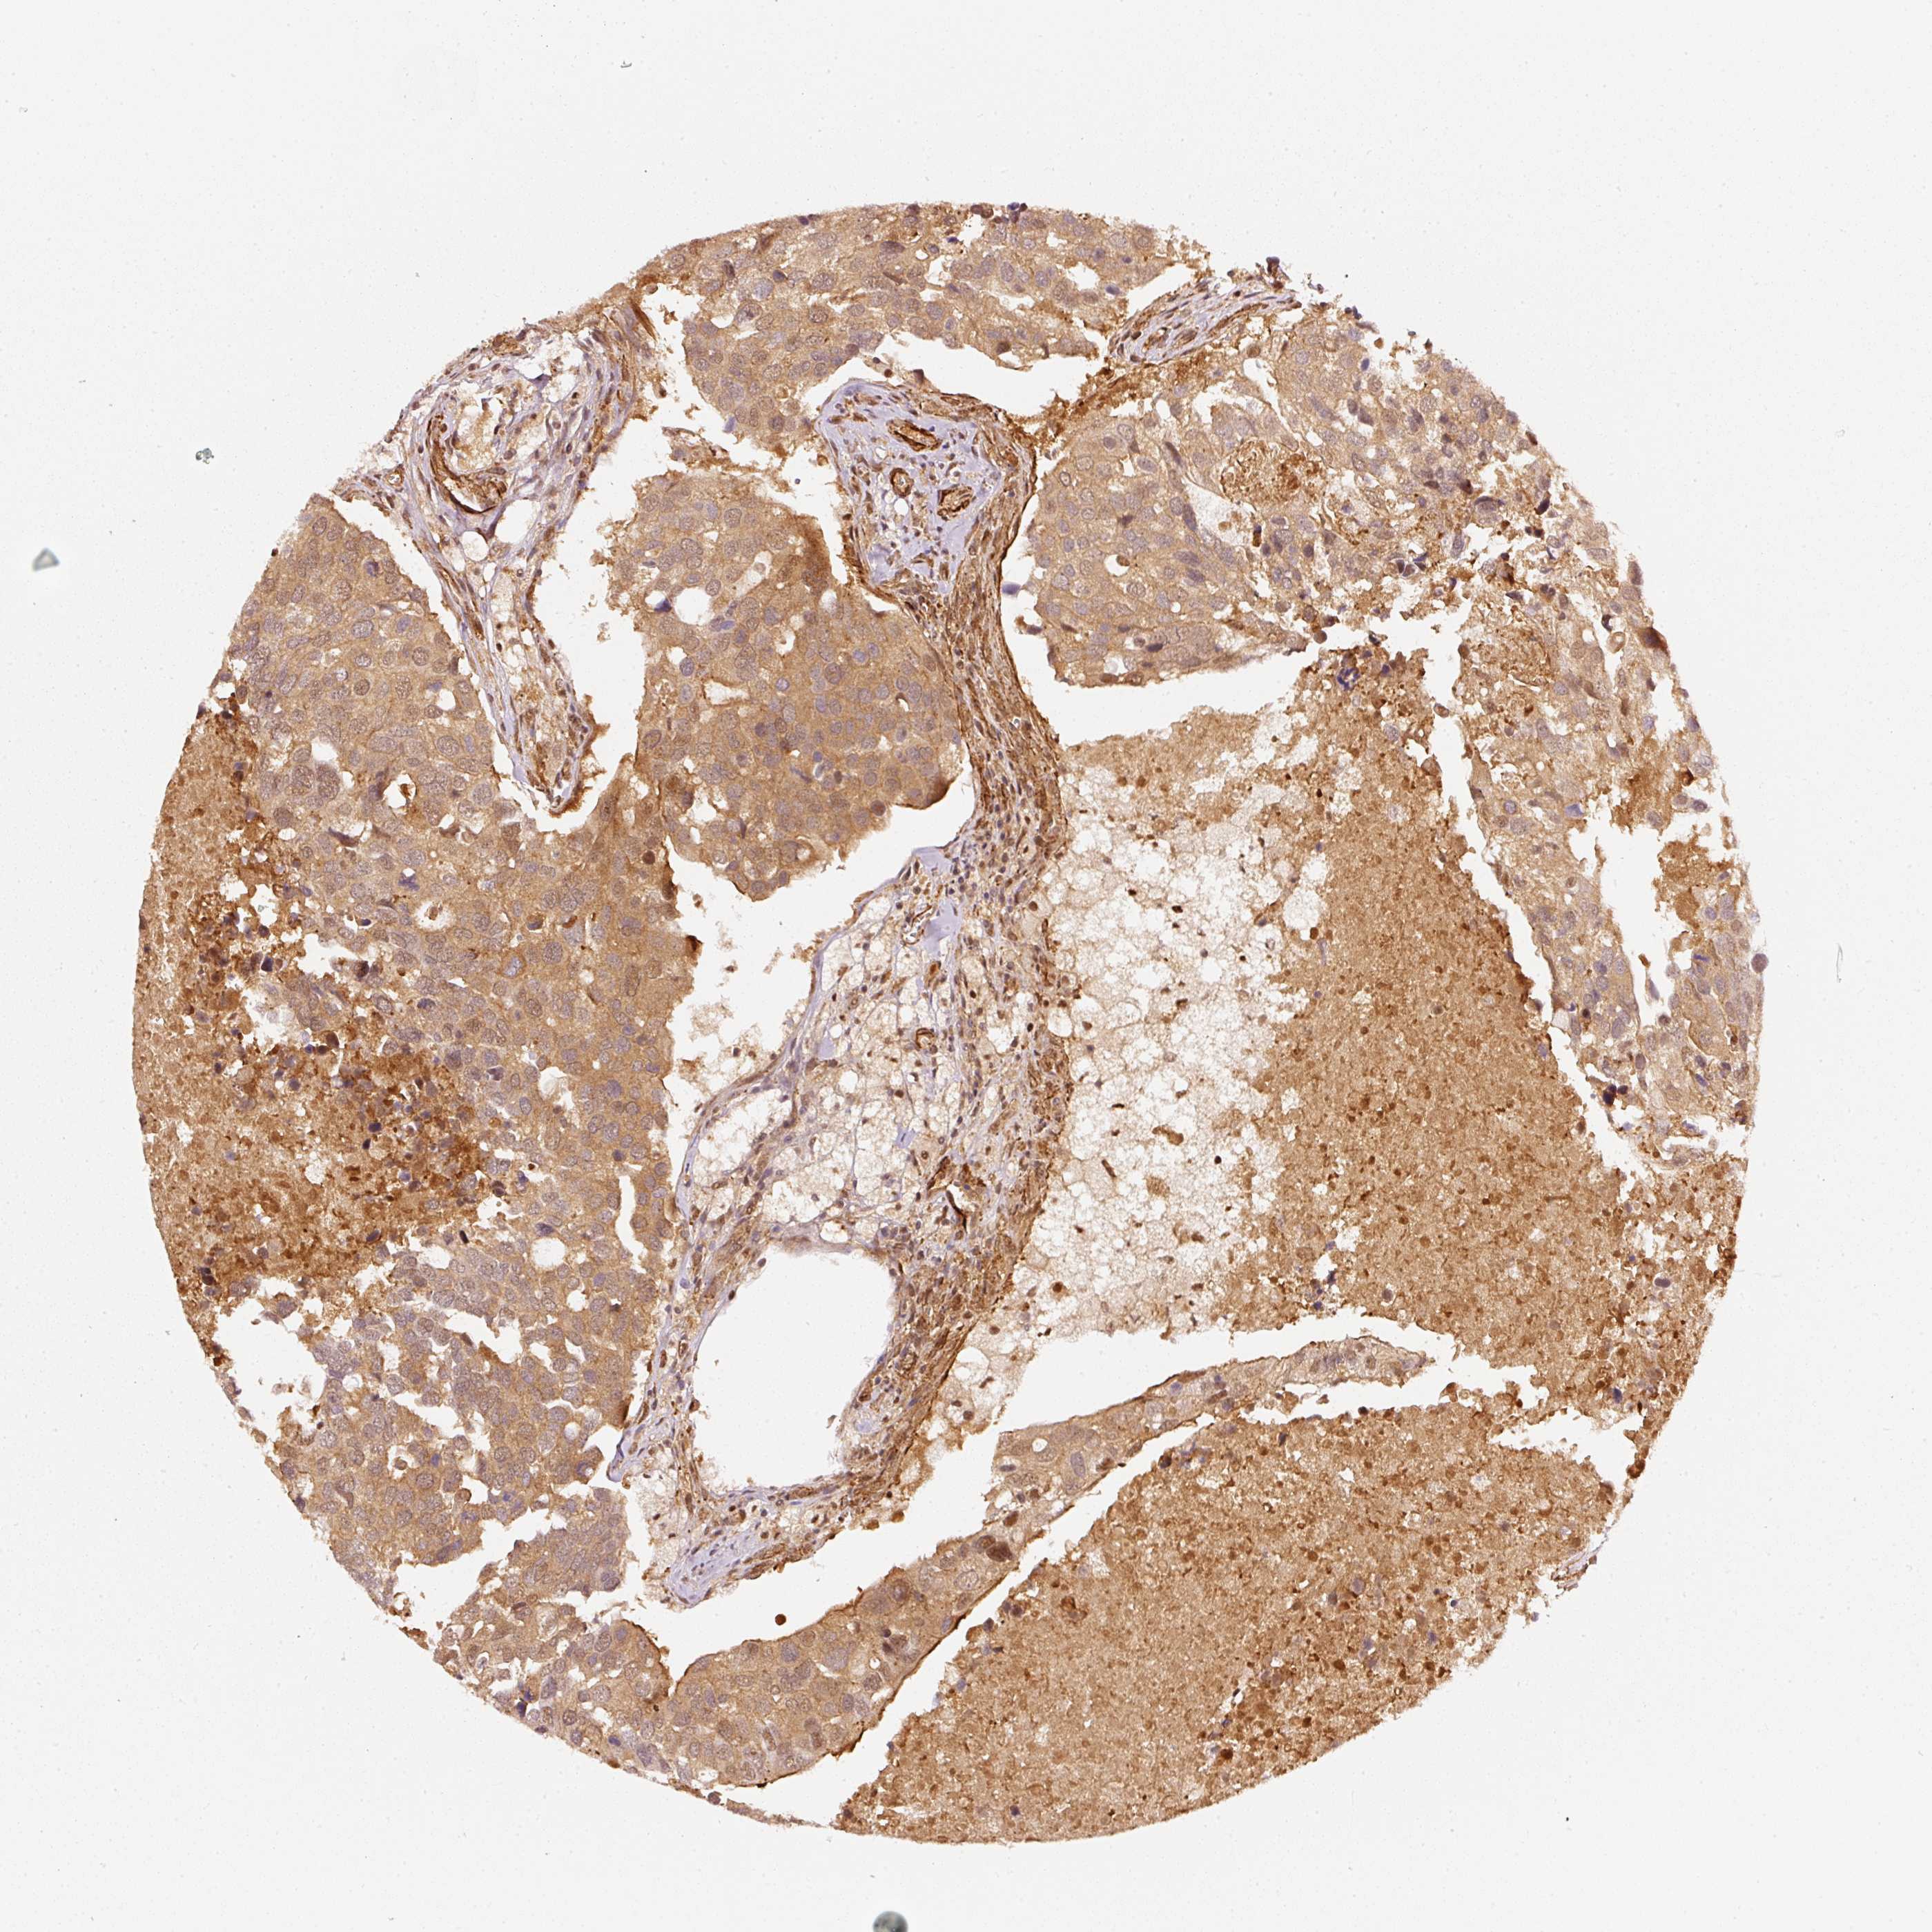

BRCA TCGA BRCA VALIDATION PROTEIN EXPRESSION

ANTIBODIES

AND

VALIDATION